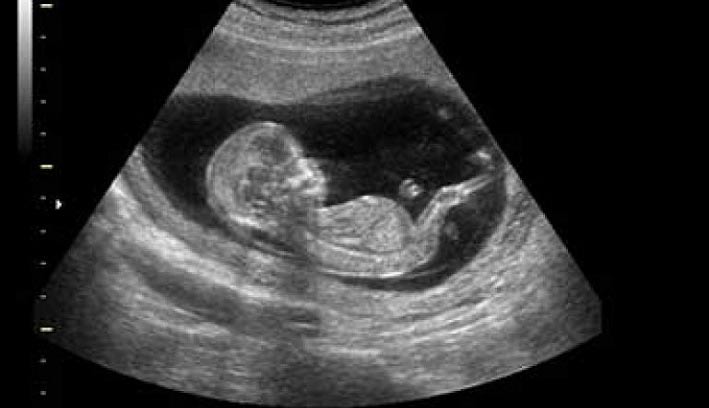

البته همه ما با معاdنه سونوگرافی در این دوران آشنا هستیم. یکی از روشهای ایمن و بی خطر که بسیاری از بانوان در دوران بارداری انجام میدهند سونوگرافی است. اما برای اطلاع از عملکرد صحیح اندامهای جنین و سلامت آن سایر معاینات را نیاز است افراد انجام دهند که در ادامه به صورت کامل در مورد آن صحبت میکنیم.

سونوگرافی غربالگری اول معمولاً بین هفته ۱۱ و ۱۳ بارداری انجام میشود. در این سونوگرافی، پزشک مقدار مایع پشت گردن جنین (NT) را اندازهگیری میکند. NT در جنینهای مبتلا به سندرم داون معمولاً بیشتر از جنینهای سالم است.